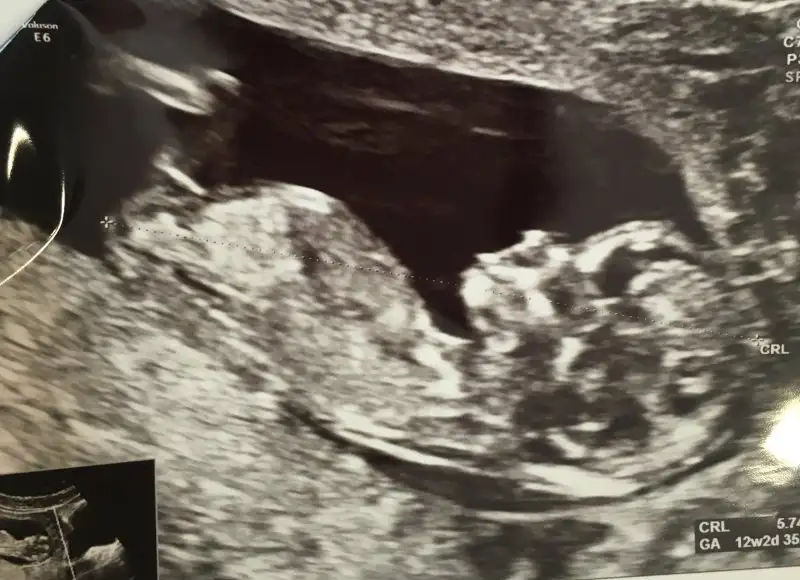

Bu da benim minis .. bakalım bende öğrenince yazarım..

13haftalik yorum yaparmisimiz?

7haftalik goruntuye gore yorum almistim :))